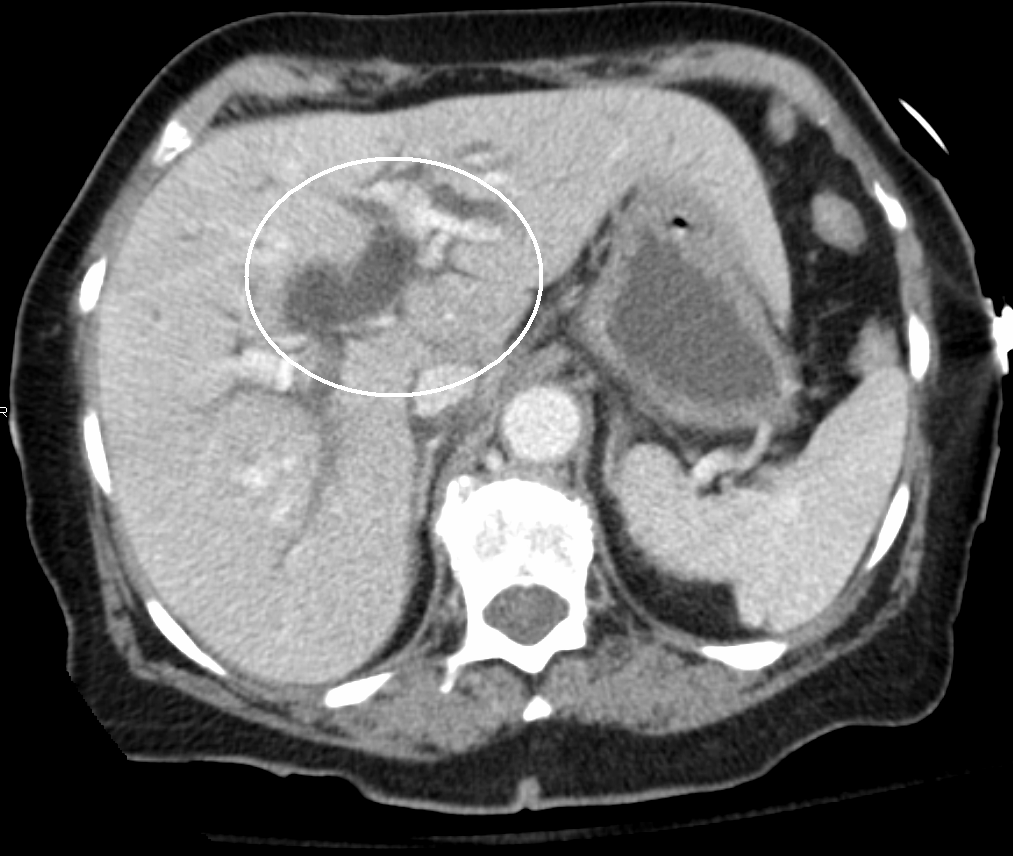

초음파, CT 스캔, HIDA 스캔과 같은 의료 영상 기법은 담관 폐쇄 여부를 확인하는 데 유용하다.[40]

초음파, CT 스캔, HIDA 스캔과 같은 의료 영상 기법은 담관 폐쇄를 감지하는 데 유용하다.[40]